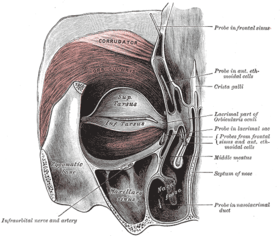

Horizontal section of nasal and orbital cavities. Left orbicularis oculi, seen from behind.

Left orbicularis oculi, seen from behind.- Cartilages of the nose, seen from below.